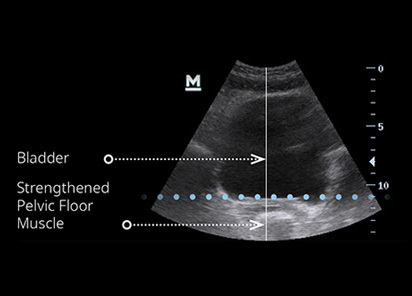

EMSELLA is a medical-grade chair that uses high-intensity electromagnetic stimulation to activate the pelvic floor muscles. During a session, you sit comfortably on the chair while targeted energy causes the muscles to contract repeatedly. These contractions are significantly stronger than those typically achieved through voluntary exercises alone. Over a course of treatment, this stimulation aims to improve pelvic floor strength, muscle coordination, and neuromuscular control. Treatment is carried out with you fully clothed and does not involve internal examination or invasive procedures.